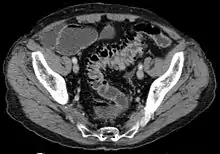

Imaging

- Contrast CT is the investigation of choice in acute episodes of diverticulitis and where complications exist.

- Colonoscopy will show the diverticulum and rule out malignancy. A colonoscopy should be performed 4–6 weeks after an acute episode.